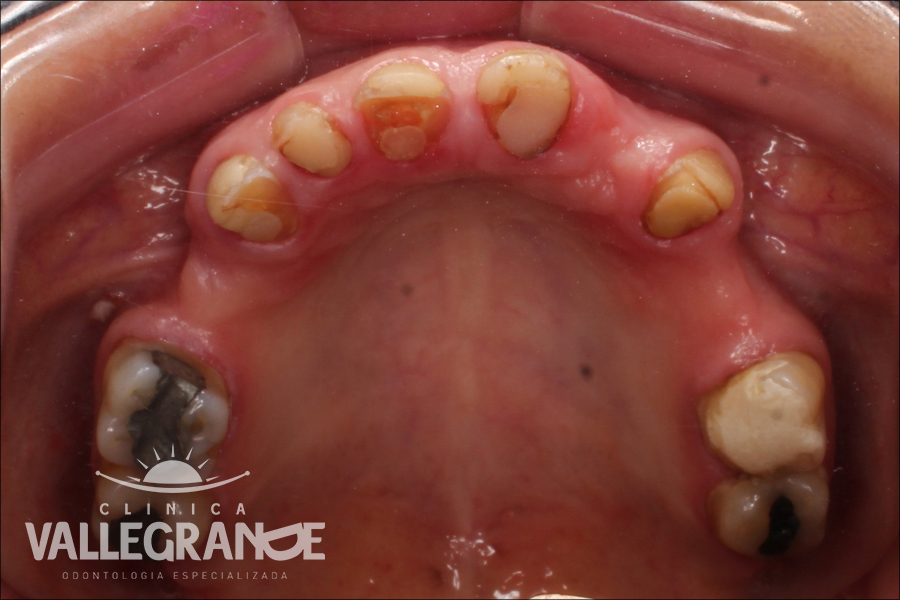

Caso de Rehabilitación Oral planificado en base a prótesis fijas unitarias(coronas) prótesis fijas plurales (puentes) y en base a coronas sobre implantes dentales . Se realizó planificación digital y se rehabilito la totalidad de la boca . No se realizó la extracción de ningún diente.